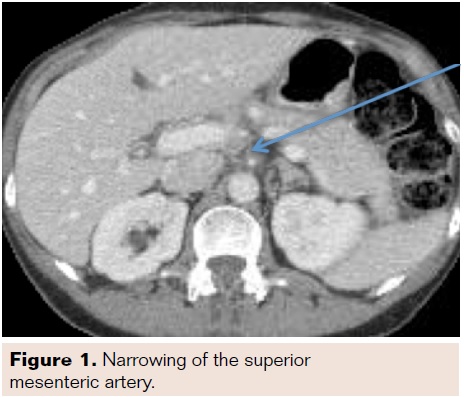

Abdominal exam revealed focal tenderness in the suprapubic region without rebound or guarding. There was no purpura or other abnormal skin findings. Vasculitis workup was not undertaken. A CT of the abdomen was performed, which showed SMA dissection within 1 centimeter from the takeoff and cecal wall thickening without signs of ischemia (Figures 1-3). No other dissection or vascular abnormality was noted. She was admitted to the vascular surgery service, made NPO, and started on a heparin infusion as well as ciprofloxacin and metronidazole for the typhlitis.

A

dedicated CT angiography of the abdomen was performed 24 hours after the initial CT due to the contrast load received on admission (as per institutional policy). The repeat scan was significant for long segment dissection of the SMA with focal contrast filling of the false lumen and a “mild-moderate” narrowing of the true lumen, which was most prominent in the mid portion of the vessel. All branches of the SMA arose from the true lumen, and again, the cecum was noted to be inflamed without pneumatosis. The patient’s abdominal exam improved over the next few days, and she was discharged home on hospital day 4 tolerating a regular diet. She was instructed to finish a course of antibiotics and to start taking warfarin after bridging with fondiparinux.